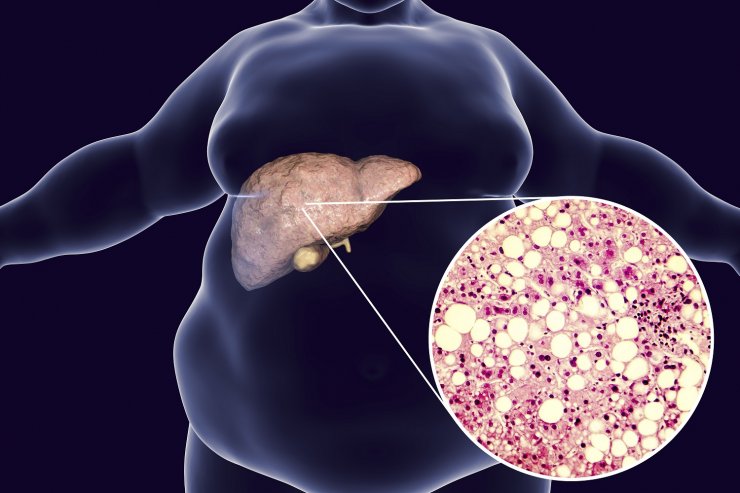

NAFLD gilt heute als die häufigste chronische Lebererkrankung weltweit. Typ-2-Diabetes mellitus (T2DM) ist ein wichtiger Risikofaktor für NAFLD und scheint auch das Fortschreiten der Lebererkrankung bei NAFLD zu beschleunigen.